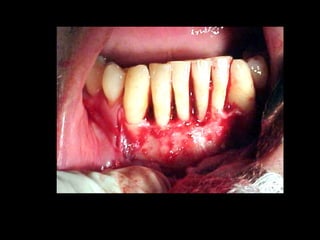

La periodontitis, denominada comúnmente piorrea, es una enfermedad que

inicialmente puede cursar con gingivitis, para luego proseguir con una pérdida de

inserción colágena, recesión gingival, e incluso la pérdida de hueso, en el caso de

no ser tratada, dejar sin soporte óseo al diente. La pérdida de dicho soporte

implica la pérdida irreparable del diente mismo.

De etiología bacteriana que afecta al periodonto (el tejido de sostén de los dientes,

constituido por la encía, el hueso alveolar, el cemento radicular y el ligamento

periodontal) se manifiesta más comúnmente en adultos mayores de 35 años, pero

puede iniciarse en edades más tempranas.

Periodontitis